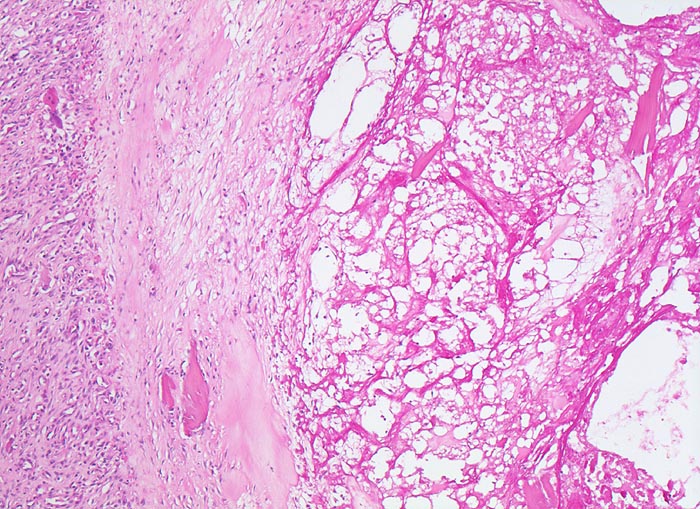

Der progrediente Knorpelverlust führt zum Freiliegen der knöchernen Deckplatte. Der subchondrale Knochen antwortet mit einer elfenbeinartigen Sklerose in Arealen vermehrter Belastung (=Eburnisation). Der traumatisierte subchondrale Knochen kann als Folge einer Knochennekrose pseudozystisch degenerieren (Geröllzystenbildung). Am Rand des Knochens, ausserhalb der Belastungszonen bilden sich irreguläre Knochenneubildungen (Randosteophytenbildung ev. mit Verdoppelung des Gelenkknorpels). Fragmentierungen dieser Osteophyten oder des Gelenkknorpels führen zu intraartikulären freien Körpern (=Gelenkmäuse) und einer Detritussynovialitis (> 1146) (> 1038) (> 539).

• Deformierte Gelenkfläche.

• Weitgehendes Fehlen des hyalinen Gelenkknorpels.

• Sekundäre Sklerose der freiliegenden Spongiosa mit Anbau von breiten Faser- und Lamellenknochensäumen an die alten Bälkchen.

• Leichte Osteoporose in der craniolateralen Entlastungszone.

• Herde von metaplastischem Faserknorpel in der Gelenkfläche.

• Randosteophyt, welcher über Resten des dort noch vorhandenen Gelenkknorpels entstanden ist (Verdoppelung des Knorpels).

• Nekrosebezirk in der Spongiosa (Geröllzyste) umgeben von einem Granulationsgewebssaum und Narbengewebe.